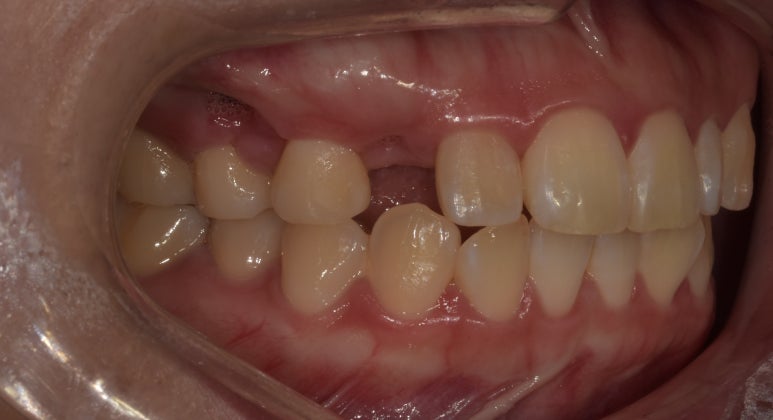

치료 전 사진

2023-03-02

처음 내원하셨을 때 환자분의 치아 사진입니다.

#13 치아가 결손된 상태였고, #22 치아는 다른 치아에 비해 크기가 작은 왜소치였습니다.

치료 전 오른쪽 치아 사진

우선은 오른쪽 10번대 치아는 #12~14를 브릿지로 연결해 #13 치아를 만들어주기로 했습니다.

치아 하나만 결손되었으니 임플란트로 치료할 수는 없는지 궁금하실텐데요.

임플란트도 가능은 하지만 현재 빈 공간이 좁은 만큼 크라운의 사이즈 역시 작아질 수밖에 없고,

뼈 구조물로 인해 뻐드러지거나 튀어나와보일 수 있는 점을 고려해 브릿지로 치료하기로 했습니다.

치료 전 왼쪽 치아 사진

20번대 치아는 #22가 왜소치인 점을 고려해 라미네이트로 치아 사이즈를 키우기로 했고,

#23 치아는 브릿지로 만들어질 #13 치아와 대칭을 맞추기 위해 치아를 약간 다듬어 라미네이트로 치료하기로 했습니다.